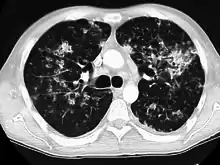

A case of miliary tuberculosis in an 82-year-old woman:

CT, 16 days after onset, showing extensive pulmonary parenchymal involvement consisting of irregular septal thickenings with ground-glass areas and centrilobular nodules with a peri-lymphatic distribution